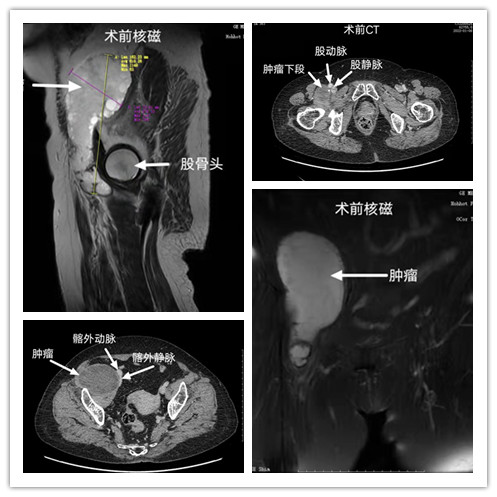

近日,我院肿瘤内科收治一例右髂窝腹膜后肿瘤患者,女性,73岁,主要症状为腹部胀痛、食欲下降,伴恶心,未呕吐,经完善腹部增强CT及盆腔增强核磁等检查,诊断为右髂窝及腹膜后肿瘤,骨盆骨质无明显破坏,良性可能性大。经胃肠外科韩俊岭副主任医师会诊后转入胃肠外科诊治,因该患者肿瘤较大,肿瘤将髂外动静脉挤压到腹腔内上方,盲肠被挤压到近肝区,肿瘤下段穿过股管,内侧与股动静脉伴行,肿瘤下级到达股骨头下方,手术完整切除难度大,如果开刀切除切口会选择右下腹至大腿前方,切口长,创伤大,患者年龄大,手术风险高,经科内讨论,白图克主任建议行腹腔镜探查、肿瘤切除术,必要时中转开放手术。

完善术前准备后,在院领导的支持下,在白图克主任指导下,由韩俊岭副主任医师主刀,在赵军副主任医师、韩慧珍副主任医师、郑海江主治医师、张亮主治医师以及手术麻醉师卢海林的协作配合下,历时5小时顺利完成完全经腹腔镜下肿瘤切除,将标本经由腹部正中小切口取出。术中因肿瘤下级深入股管,位置极深,显露术野困难,且有股动静脉及神经等伴行,手术非常困难,但在我科医师团队及兄弟科室的精诚配合下,手术顺利完成,术后病理回报(后腹膜)良性囊肿,纤维囊壁玻璃样变性,未见明显被覆上皮。